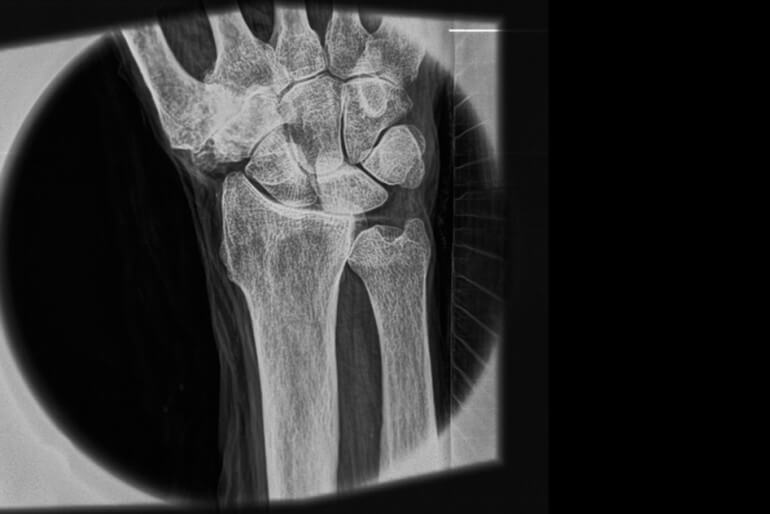

Новая технология рентгенографии позволяет делать качественные снимки мягких тканей

Новая система, разработанная совместными усилиями научных сотрудников Массачусетского технологического института и Центральной больницы штата Массачусетс мало того, что достаточно компактна для того, чтобы ее можно было назвать портативной и облучает пациента куда меньшим объемом радиации, так еще и способна делать изображения мягких тканей организма в высоком разрешении.

В результате происходит более широкое и равномерное распределение лучей, и у машины появляется возможность отображения мягких тканей без какой-либо необходимости у пациента в приеме специальных контрастирующих агентов (некоторые из них требуют подготовки перед приемом, а некоторые — могут быть даже опасными для пациента). Кроме того, в отличие от традиционных громоздких рентгеновских аппаратов, новое устройство можно быстро подготовить к работе. В этом случае даже не требуется разогрев аппарата.